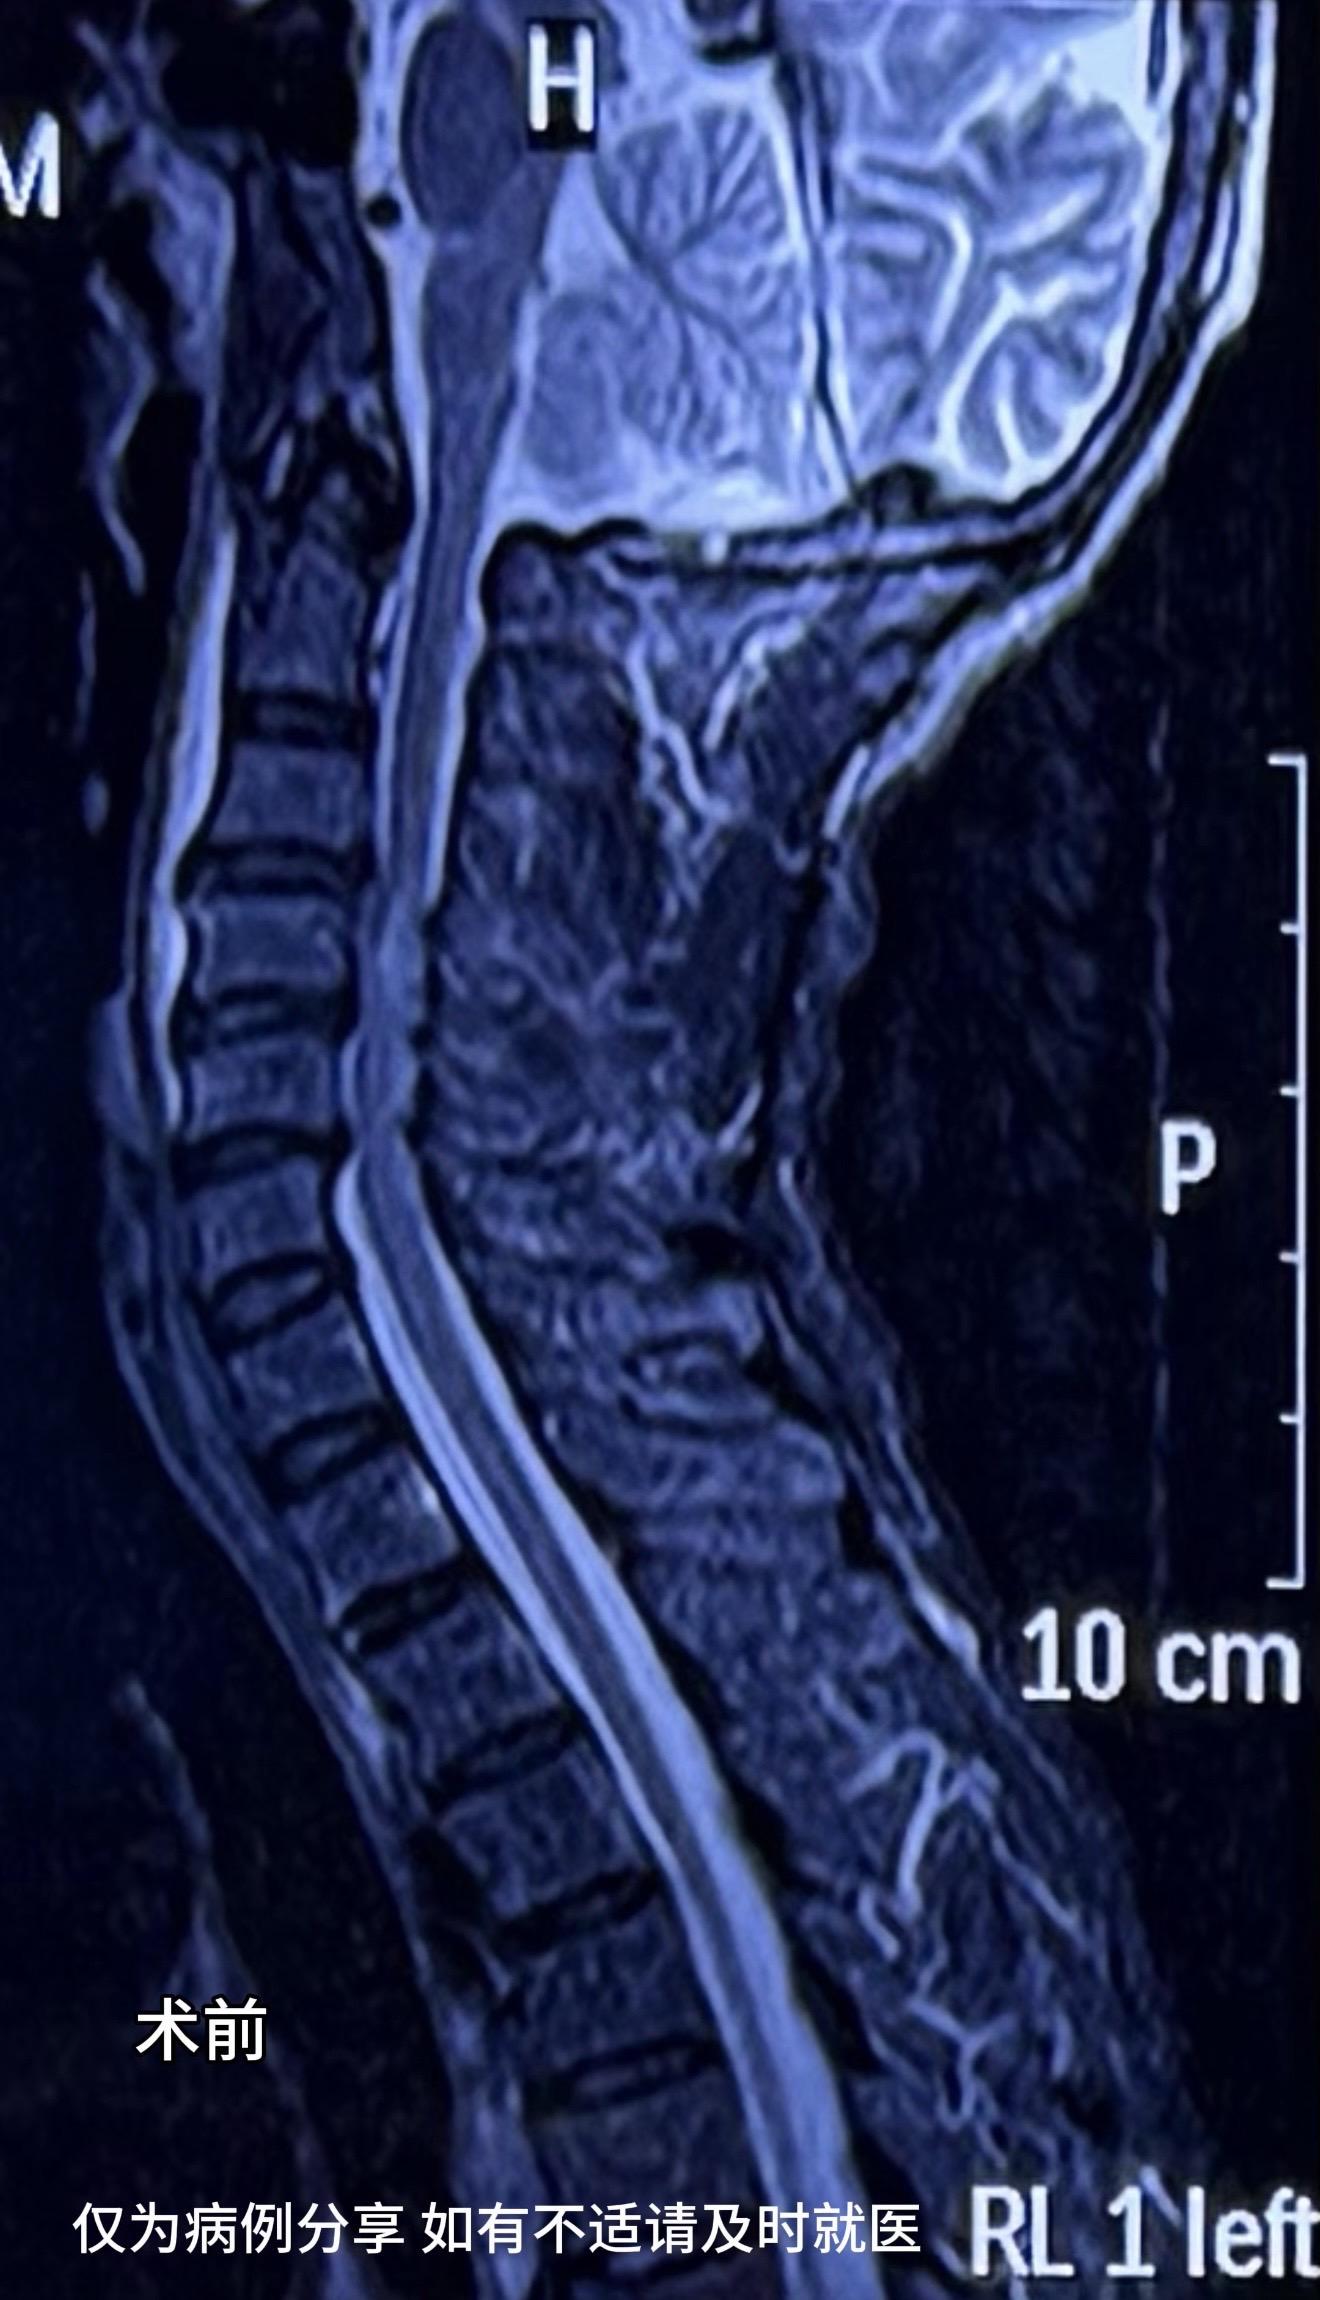

60多岁男性,工地颈椎外伤,伤后双手握力下降,右手握力2级,持碗筷不能,生活受限明显。术后6天,右手握力恢复至4级弱,能持碗筷,患者及家属非常满意。